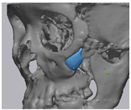

2.2. Computer-Aided Virtual Surgery, Design, and Fabrication of Patient-Specific Devices

2.5. Cone Beam CT and 3D Comparison

3.2. Fusion Rate Analysis Using 3D CT

3.3. 3D Comparison between Immediate Post Operative and 6 Months Post Operative